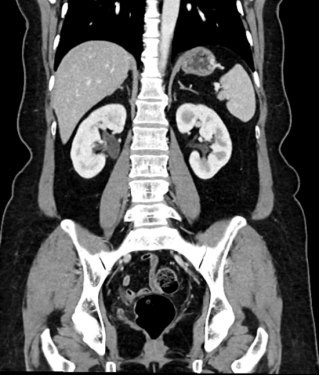

李女士术前CT

李女士术前造影